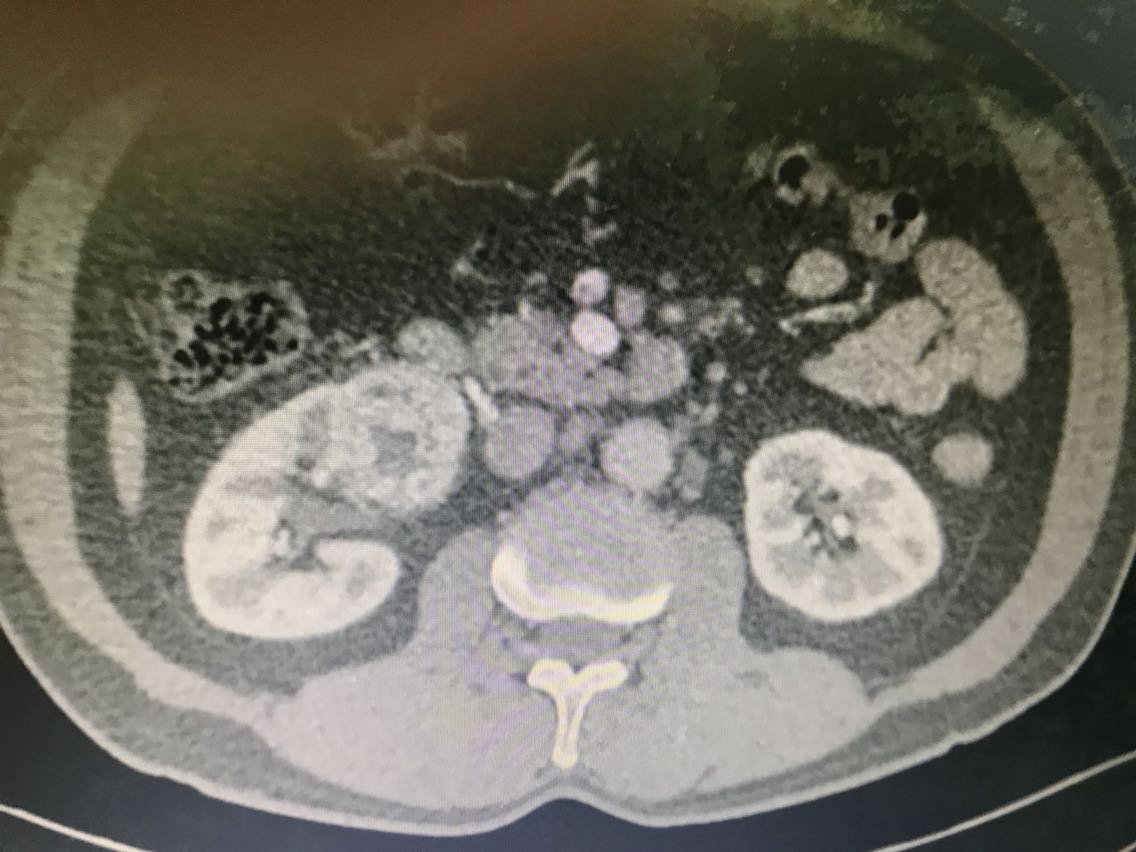

患者男性,62岁。 主诉:咯血、体检发现右肾占位1+月 现病史:1+月前,患者无明显诱因出现反复咯血,为痰中带鲜血,无胃内容物,无畏寒、发热,无胸闷、胸痛,无潮热盗汗,无恶心、呕吐,无腹胀、腹痛等不适。于当地医院就诊,行相关检查(具体报告未见)考虑“支气管扩张”,行相关治疗(具体不详)后患者咯血症状好转出院。患者于住院期间检查发现右肾占位(报告未见),无腰痛、腰胀,无血尿、蛋白尿,无尿少及排尿困难。患者为进一步诊治,于我院门诊就诊,查肝肾功能、肿瘤标志物、小便常规未见明显异常。上腹部增强CT:右肾前下份占位,考虑透明细胞癌(T3aN2Mx),左肾结石、囊肿,腹膜后多发淋巴结,肝脏右后叶下段小囊肿,腹主动脉管壁钙化。现患者为进一步明确诊断及治疗,入住我科。 既往史无特殊。

查体无特殊。 辅助检查: 心电图:窦性心律,电轴左偏,左前分支阻滞,不完全性右束支阻滞。 上腹部增强CT:右肾前下份占位,考虑透明细胞癌(T3aN2Mx),左肾结石、囊肿,腹膜后多发淋巴结,肝脏右后叶下段小囊肿,腹主动脉管壁钙化。